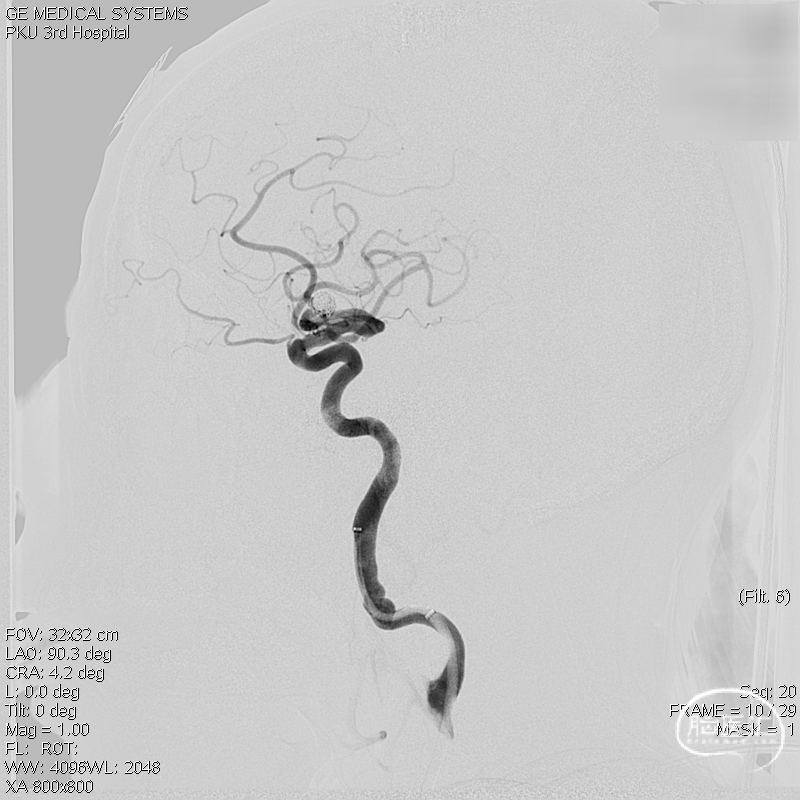

复查标准正侧位造影, ICA、MCA、ACA主干及远端分支良好,动脉瘤栓塞满意。

术后工作位+侧位造影

术后三维重建,支架贴壁良好,动脉瘤完全栓塞。